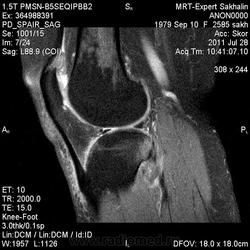

Коленный сустав

Подглядела случай у коллеги.

Что это может быть?

участки гемопоэтического костного мозга